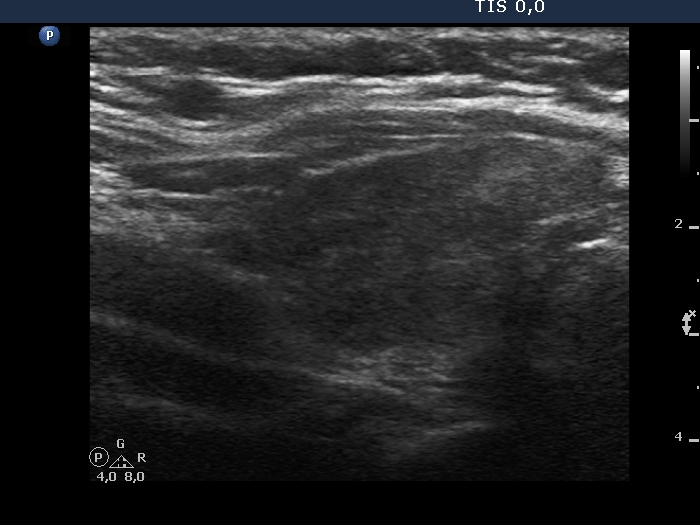

Lymphocytic thyroiditis - case 1442

Follow-up examination 7 years after the first one (ultrasonographic picture 5)

Left lobe, longitudinal scan.